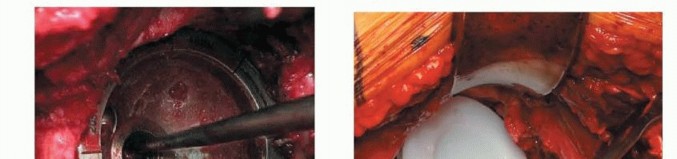

الشكل التوضيحي 2: تحضير الحُق. أ. التجويف الأولي لتوسيع الحُق بالكامل. ب. التجويف مكتمل للجدار الإنسي. ج. يستمر التجويف بشكل متسلسل بزاوية تبعيد 35 إلى 45 درجة و10 إلى 20 درجة من التدوير الأمامي.

يجب أن يتم التجويف الأولي بضغط معتدل حتى يتم تقييم جودة العظم. الهدف من التجويف الأولي هو توسيط المجوّف بالكامل. يجب إزالة الحفرة الكوتيلويدية دون اختراق الجدار الإنسي. ثم يستمر التجويف بشكل متسلسل. الهدف هو إعادة إنشاء مركز الدوران عن طريق وضع الجانب السفلي الإنسي للمقبس عند مستوى علامة الدمعة مع ميل المكون بزاوية 35 إلى 45 درجة، مع 10 إلى 20 درجة من التدوير الأمامي وتثبيت مبدئي جيد يتم الحصول عليه عن طريق التثبيت بالضغط.